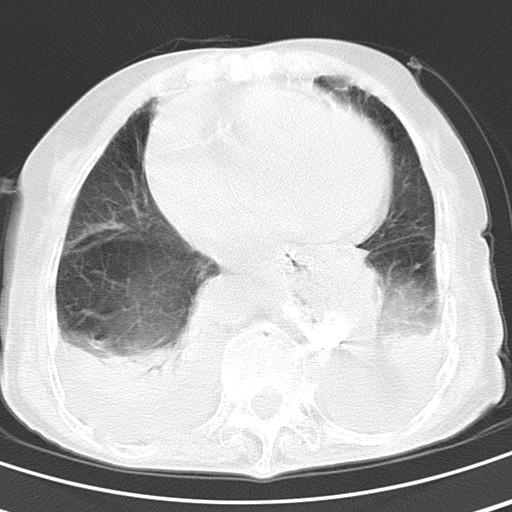

女,93岁,摔伤后检查。

右肺炎症,心功能不全伴双侧胸腔积液,右下肺膨胀不全,食管裂孔疝,冠脉钙化,心包少量积液,左侧肋骨骨折,请上传骨窗.

双肺感染合并双侧胸腔积液、胸膜增厚粘连,骨性胸廓未见明确骨折征。

右侧锁骨\\肩胛骨骨折、右侧湿肺,心功能不全伴双侧胸腔积液,右下肺膨胀不全,左膈破裂或食管裂孔疝,冠脉钙化,心包少量积液,请上传骨窗.

右肺炎症,心功能不全伴双侧胸腔积液,右下肺膨胀不全,食管裂孔疝,冠脉钙化,心包少量积液,左侧肋骨骨折,右肩甲骨粉碎性骨折。93岁,高寿哇!

右肺炎症,心功能不全伴双侧胸腔积液,右下肺膨胀不全,食管裂孔疝,冠脉钙化,心包少量积液,左侧肋骨骨折,右肩甲骨粉碎性骨折。